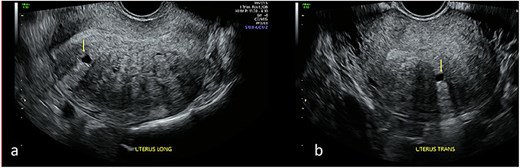

Repeat specialist ultrasound (Fig. 1) identified a right interstitial ectopic pregnancy measuring 27 × 24 × 26 mm, with a decidual reaction, a foetal pole and absent cardiac activity. The gestational sac did not communicate with the endometrial cavity. Diffuse cystic adenomyosis was noted (Fig. 2). Retrospective review indicated that sub-endometrial microcysts had been mistaken for a gestational sac on earlier scans (Fig. 3).

Transvaginal ultrasound of the uterus demonstrating adenomyotic spaces in the myometrium and sub-endometrial border in longitudinal (a) and transverse planes (b), with a notable absence of decidual reaction around the cystic spaces.